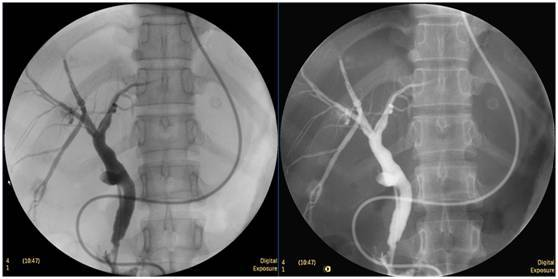

膽囊結(jié)石

ERCP膽囊顯影,見多枚結(jié)石影。

鼻膽管造影

立位注入造影劑,膽總管顯影好,稍擴張,未見結(jié)石影。

膽總管結(jié)石

柱狀球囊擴張完全,膽總管擴張,下段見充盈缺損影。

膽總管擴張,下段見明顯充盈缺損(上圖為反片且局部放大后效果)

柱狀球囊擴張膽總管下段及乳頭(上圖為使用取石網(wǎng)籃取石)。